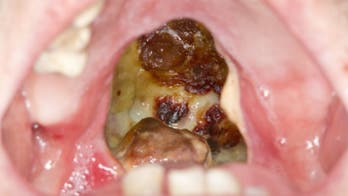

September 9, 2019 Cocaine burned massive hole in man's throat before untimely death: report The graphic aftermath of his cocaine use was documented in BMJ Case Reports.